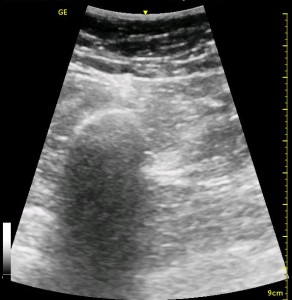

The following ultrasound image shows typical relationships of the sonoanatomy of the anterior sciatic nerve block. The femur is at 4cm on the right (lateral) of the image seen as a bright white horizontal line. Typically, there is a bone shadow below it, though there is some artifact below the femur here. The femoral vessels are seen between the 2cm and 3cm marks just to the right of center as a darkened area. They really can be determined by pausing for the appearance of arterial pulsation and venous compressibility. The adductors are seen to the left of the femur as a darkened area. Just deep to this between the 6cm and 7cm mark is a brightened rectangular shape, the sciatic nerve. The brightness fill fade with rocking of the probe over it. The nerve can be approached from the medial or lateral aspect of the probe, and moving the probe medially will sometimes allow for a better trajectory.

The image above is not an obvious one, and I did that on purpose. You have to get used to the idea that you will not always have a ‘super distinct’ image with this approach, and you will often need to use a number of additional clues to find your target and then to put local around it. I think the only way to really get a handle on being able to identify the basic elements is to look at several images over and over, so I have provided several below for you to use for practice. Note that the sciatic nerve will ‘poke out’ from behind the femur to different degrees depending on your orientation to the femur as well as to how far up or down the femur you go. It will be seen more if you are proximal. See how well you can identify the structures in the images below.